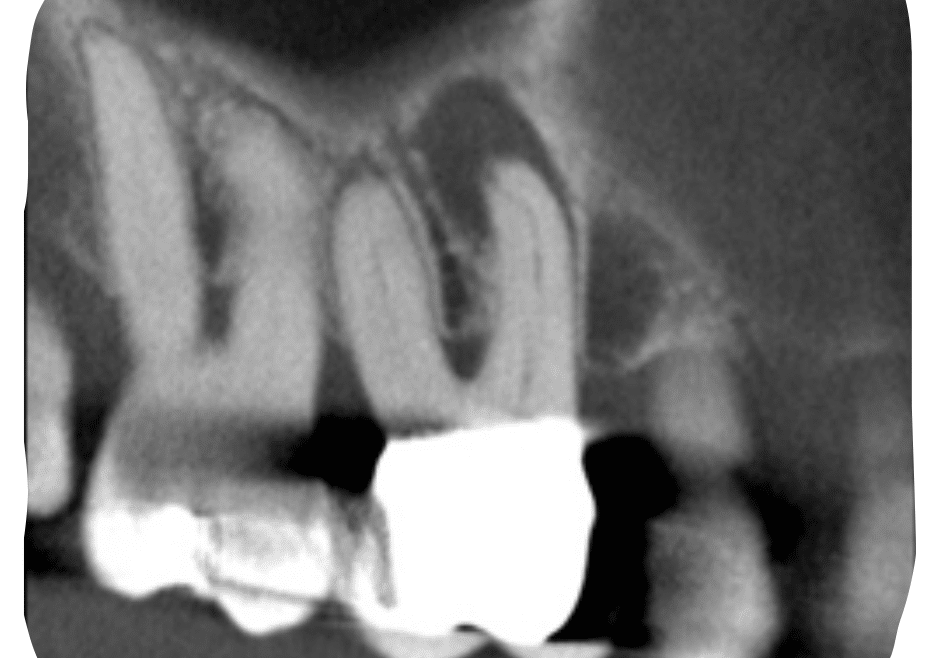

Case Study by Dr. Randy Cross

EndoScore of 3 at finish. Necrotic Symptomatic Apical Periodontitis. 2 visit with triple antibiotic paste, 30x06 conserve file with matching GP and Endoceramic sealer. Finished with bonded VistaApex clear flowable. The patient is being recalled in one year to confirm healing.

EndoScore: 3